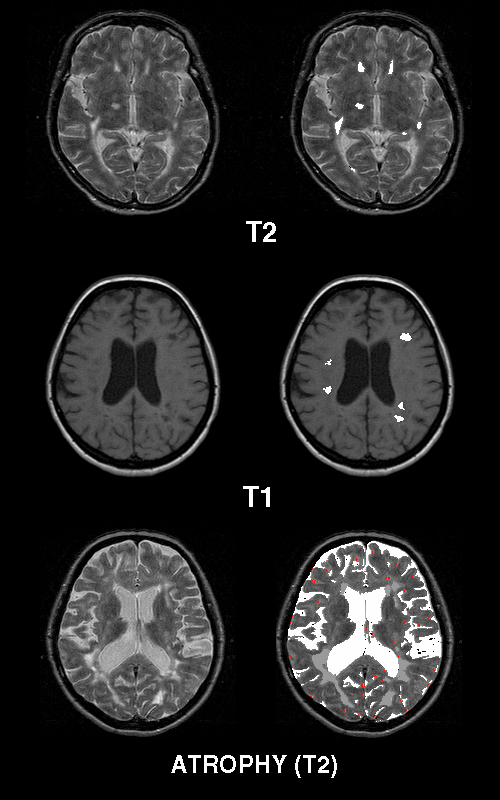

A third example is the localization of multiple sclerosis plaques in the white matter of brain after segmentation

(Fig 4). This type of an approach is currently used to follow the possible effect of beta-interferon treatment

of MS patients (Dastidar P. et al. 1999).

Figure 4. Axial T1 and T2 weighted MRI sections of MS plaques and brain

atrophy.